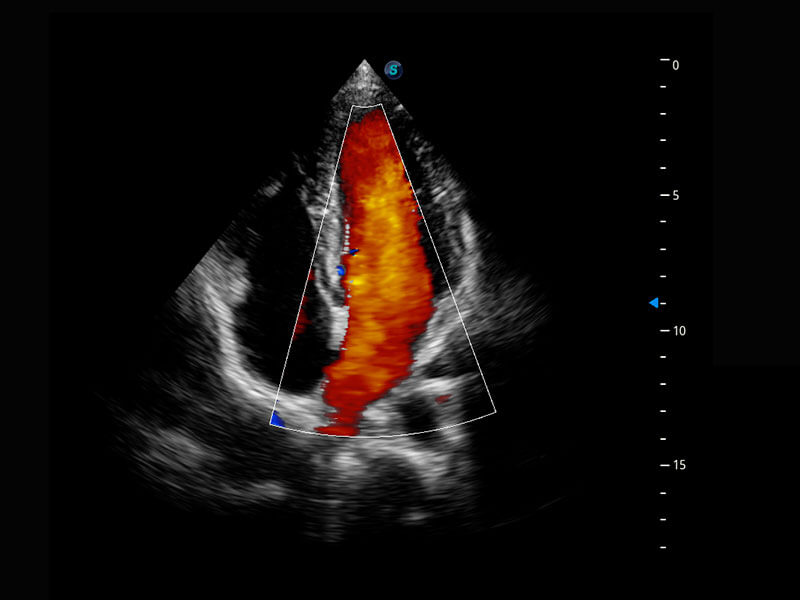

• 四腔心血流

• 右室双出口